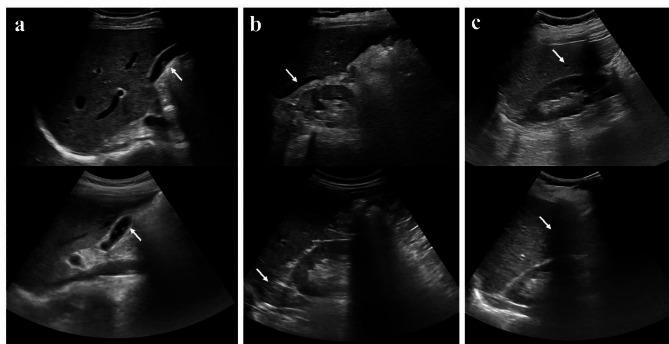

To investigate the feasibility of robot-assisted teleultrasound diagnosis for radioactive patients compared with conventional ultrasound diagnosis. In this prospective study (ChineseClinicalTrials.gov identifier, ChiCTR2200057253), 32 radioactive patients were examined by conventional ultrasound and MGIUS-R3 robot-assisted ultrasound from March 2022 to June 2022. After two scans, patients completed a satisfaction survey, including comfort score, fear score, tension score and pain score. The durations of both scans were recorded, and sonographers wore lead apron to prevent the radiation during the conventional examination. Subsequently, the ultrasonic images saved by sonographers were diagnosed and scored. Finally, we evaluated the feasibility of the robot-assisted teleultrasound diagnosis system regarding patients' satisfaction, examination duration, image quality and diagnostic consistency via χ test, Kappa consistency test and Wilcoxon signed-rank test. Among 32 patients (mean age, 54.9 ± 9.8 [SD]; 16 women), 29 had consistent diagnoses and 3 had inconsistent diagnoses between two scans, but the diagnostic consistency was good (Kappa = 0.818, P < 0.001). In addition, there was no statistical difference between two scans with regard to image quality score (29.28 ± 0.47vs29.31 ± 0.44, P = 0.97), comfort score (10vs10, P > 0.99), tension score (0vs0, P > 0.99) and fear score (0.09vs0, P = 0.32). Although 7 patients felt slightly painful during teleultrasound scan, the pain intensity was acceptable (0.31vs0, P = 0.02). The mean duration of teleultrasound examinations was 11.1 min (6-24 min), which was longer than 5.9 min (2-17 min) of conventional examinations (P < 0.001). Comparing robot-assisted teleultrasound and conventional ultrasound, there was no evidence of differences regarding patients' satisfaction and image quality, and the diagnostic consistency was remarkable.

研究机器人辅助远程超声诊断放射性患者相对于传统超声诊断的可行性。在这项前瞻性研究(中国临床试验注册中心标识符,ChiCTR2200057253)中,2022年3月至2022年6月期间,对32例放射性患者进行了传统超声检查和MGIUS - R3机器人辅助超声检查。两次扫描后,患者完成了满意度调查,包括舒适度评分、恐惧评分、紧张度评分和疼痛评分。记录两次扫描的时长,在传统检查过程中超声检查人员穿着铅围裙以防止辐射。随后,对超声检查人员保存的超声图像进行诊断和评分。最后,我们通过χ检验、Kappa一致性检验和Wilcoxon符号秩检验,从患者满意度、检查时长、图像质量和诊断一致性方面评估机器人辅助远程超声诊断系统的可行性。32例患者(平均年龄54.9±9.8[标准差];16名女性)中,两次扫描间29例诊断一致,3例诊断不一致,但诊断一致性良好(Kappa = 0.818,P < 0.001)。此外,两次扫描在图像质量评分(29.28±0.47对29.31±0.44,P = 0.97)、舒适度评分(10对10,P > 0.99)、紧张度评分(0对0,P > 0.99)和恐惧评分(0.09对0,P = 0.32)方面无统计学差异。尽管7例患者在远程超声扫描时有轻微疼痛,但疼痛强度可接受(0.31对0,P = 0.02)。远程超声检查的平均时长为11.1分钟(6 - 24分钟),长于传统检查的5.9分钟(2 - 17分钟)(P < 0.001)。比较机器人辅助远程超声和传统超声,在患者满意度和图像质量方面没有差异的证据,且诊断一致性显著。